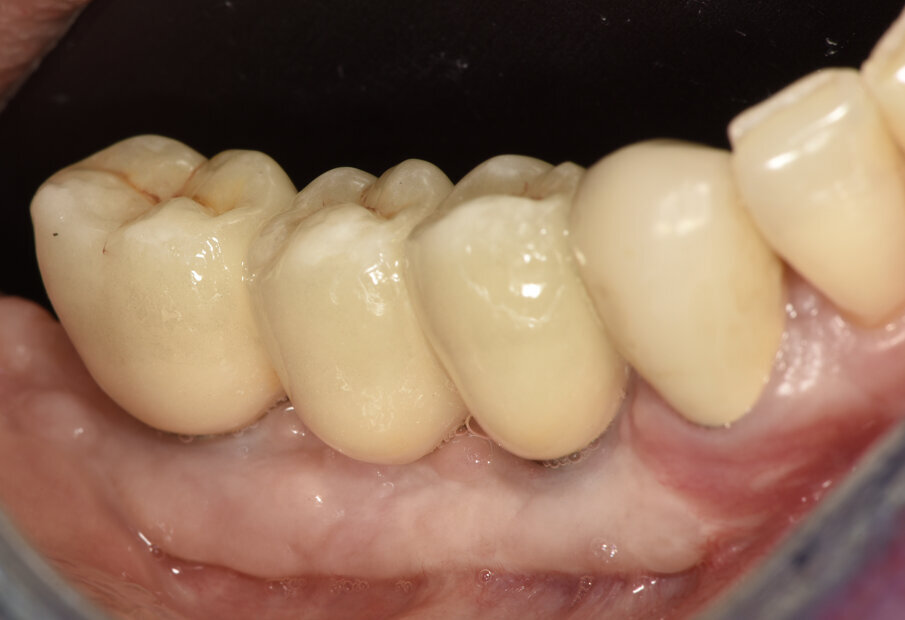

I due impianti (4 x 10 in sede 4.4 e 4 x 8.5 in sede 46 – Nobel Biocare AG – Kloten, Switzerland) sono stati inseriti con modalità sommersa e con un torque di 45 Ncm. Al momento della rimozione della griglia (Fig. 10) non è stata visibile alcuna significativa perdita ossea e il tessuto osseo rigenerato è apparso di notevole consistenza, tanto che alcuni frammenti della periferia della griglia, completamente ricoperti da osso neoformato, sono stati lasciati in situ per evitare rimozione di tessuto osso e perché non interferivano con l’inserimento implantare. L’analisi istomorfometrica del prelievo osseo eseguito con una fresa iniziale cava di 2.5 mm nel futuro sito implantare in posizione 4.4, ha mostrato la presenza di una matrice vitale e densa e senza focolai infiammatori. Durante la fase di riapertura degli impianti, eseguita a gennaio 2019, a causa di una inadeguata banda di mucosa cheratinizzata sul versante vestibolare, è stato eseguito un intervento di vestiboloplastica mediante affondamento di fornice e innesto epitelio-connettivale prelevato dal palato. A distanza di due mesi sono iniziate le fasi protesiche (Fig. 11). Le corone protesiche sono state cementate sui monconi implantari a maggio 2019 ed è stata eseguita una radiografia endorale di controllo (Figg. 12a, 12b). Le fasi protesiche sono state eseguite dal dott. Razzini.

Figg. 12a, 12b_Immagine clinica e radiografica che mostrano il manufatto protesico finale.